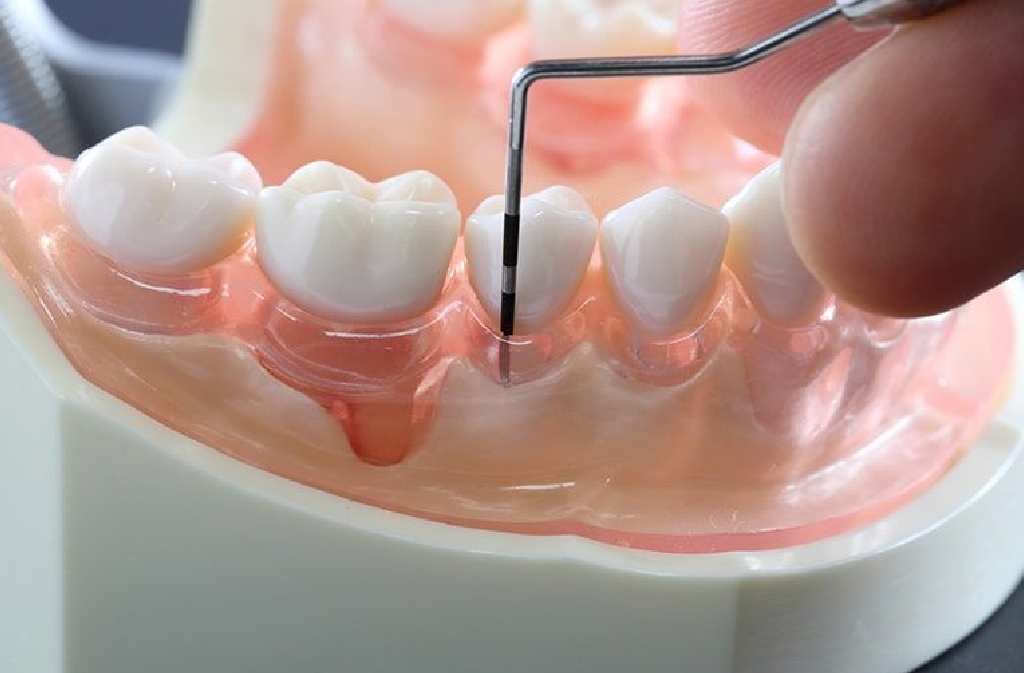

牙周病的檢查目的就是要了解患者牙周病的嚴重程度,以利訂定治療的計畫。檢查分兩項:第一項,測量牙周囊袋的深度,了解牙周病破壞的深度。第二項,拍攝全口X光片,了解牙齒周圍還剩多少骨頭,評估牙齒的預後。

探測牙周囊袋的深度